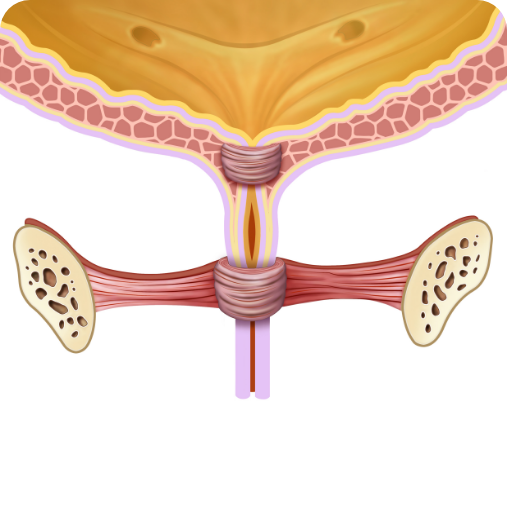

PRED kúrou:

Slabé svaly močovej trubice

PO kúre:

Silné uretrálne svaly